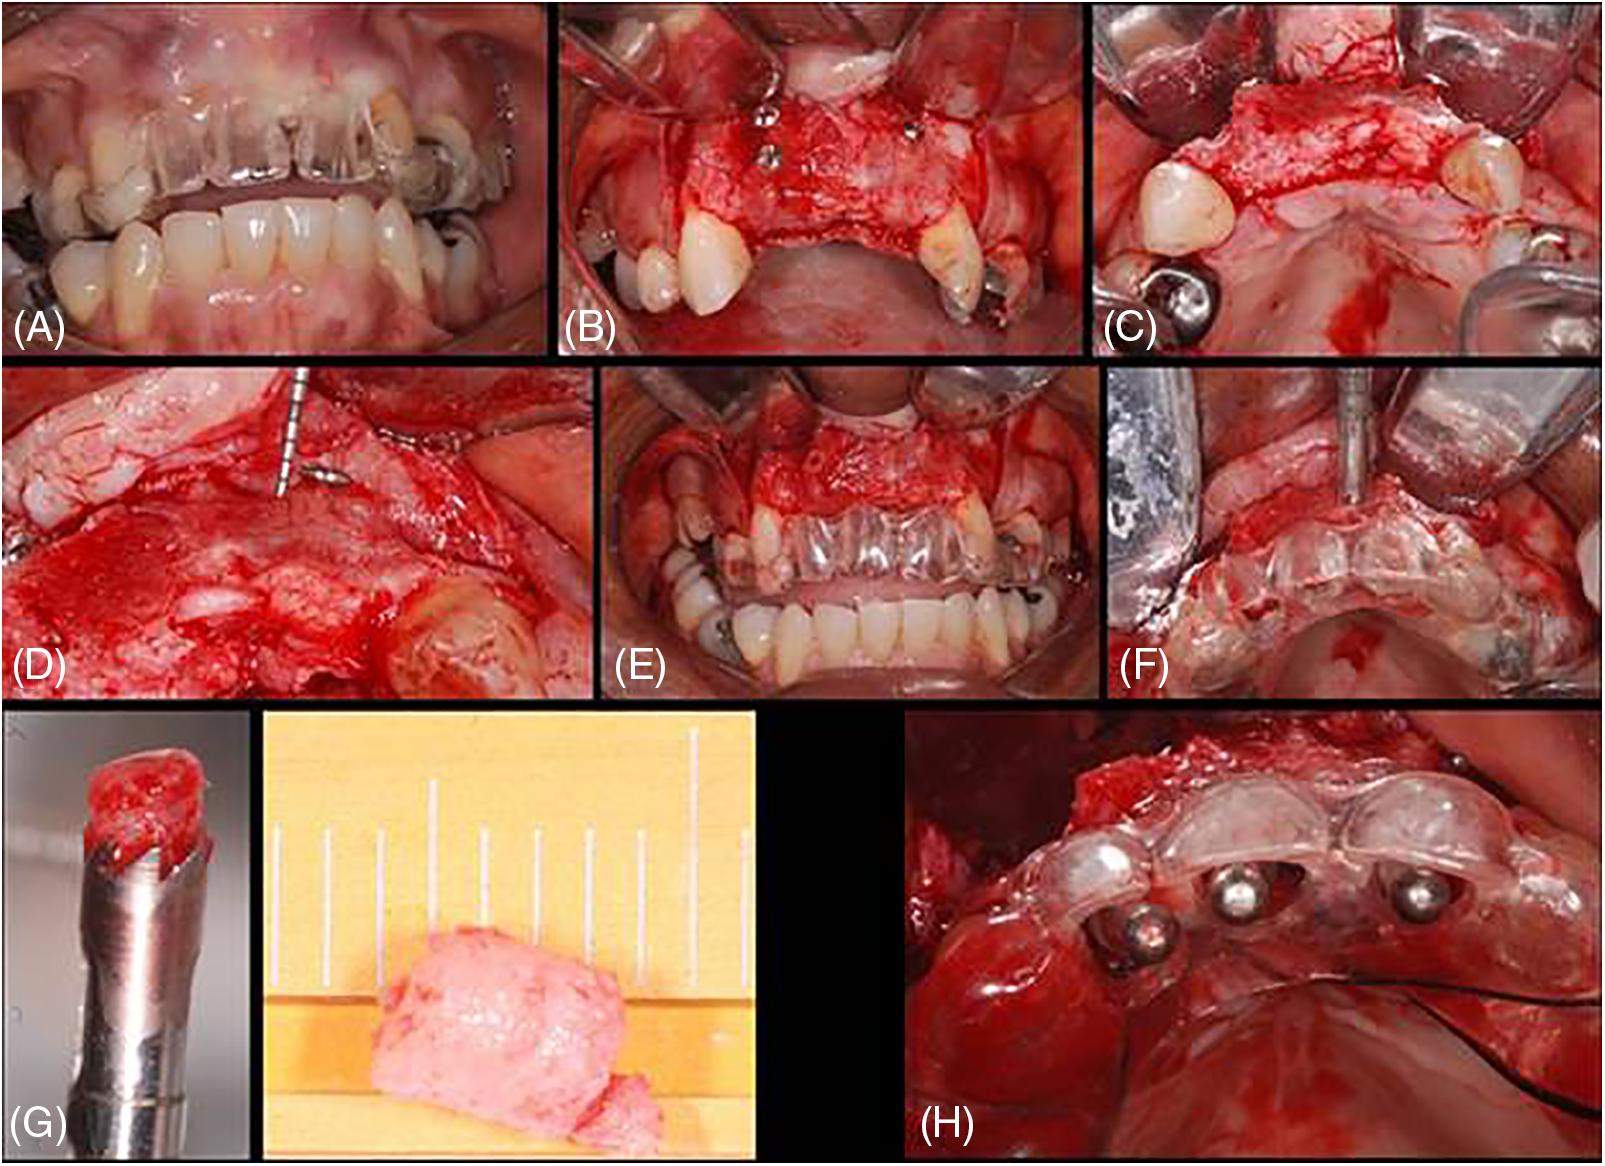

Figure 3: Case 3. Sequential images for the treatment: (A) surgical guide proof before surgery; (B) flap raised and blocks bone grafts placed (immediate thickness presented); (C–E) after around 6 months, sequential images of the trephine collecting material and material after harvested; (F–G) seven implants were placed to rehabilitate the patient

Figure 8: Case 8. Sequential images for the treatment: (A) surgical guide proof; (B–D) blocks exposed and integrated with ~1.0 mm of horizontal loss (periodontal probe); (E) screws removed; (F–G) sample collected with trephine; (H) guide in position for the implant placement

The cases were performed following the same sequence, varying the quantity and size of bone used to reconstruct but always keeping the same type of donor region (tibia), e.g., Fig. 1 shows 2 block bone grafts, and Fig. 3 with three blocks. Figs. 1–3 show the procedures done in all of them. Initially, a panoramic X-ray was requested for the primary assessment and overview (Figs. 1 and 2). CBCT was sequentially assessed to verify the necessary dimensions and volume of the bone graft. The surgery was scheduled after receiving the bone graft, and the surgical guide for the implant placement was prepared (Figs. 3 and 8).

The flap was raised according to the needed extension, and the receptor bedside was prepared to receive the homologous bone graft from the tibia. The block graft had an adequate cortical width (≥5 mm), length, height, and medullar area. After adjustments, the homologous bone was fixed using at least 2 screws, transfixing both cortical (buccal and lingual) of the bedside receptor. The immediate osseous volume obtained during the surgery was adequate for posterior rehabilitation (Figs. 1–8); therefore, after the healing period (between 5 and 12 months), a volume loss was expected and found due to tissue remodeling (Fig. 8). After the healing period, the patients were recalled for a new evaluation and panoramic/CBCT analysis (Figs. 1 and 2). Afterward, the surgical procedure for implant placement was scheduled, where the block was trephined to obtain the samples for histological processing (Figs. 1–3 and 8; macroscopic aspects of the histological piece [4 ø mm × 4 mm height]). The implant placement occurred without a significative event, except in one case, in which a small fracture in the block graft was observed (Fig. 2) during the implant installation (after healing); this fact did not harm the procedure and rehabilitation.